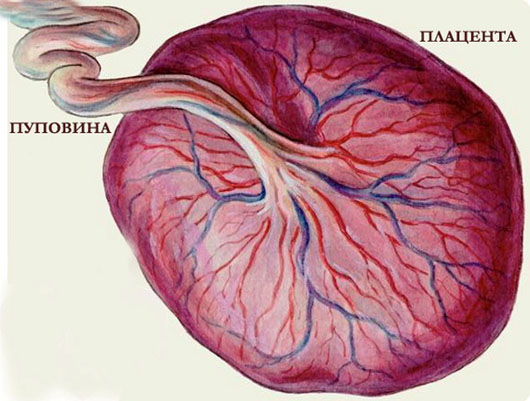

Роль плаценты, плодного пузыря и пуповины

Плацента (детское место) — это самый важный орган, благодаря ему наш зародыш питается, дышит, она выводит все отработанные продукты, берет на себя функции легких, органов пищеварения, почек, кожи.

После 16 недели (первые 16 недель плацента только формируется вместе с ростом ребенка, в это время мамины железы вырабатывают все гормоны на двоих) плацента становится еще и железой, которая вырабатывает все нужные малышу гормону.

Кроме того, она защищает малыша от многих вредных веществ, болезнетворных микробов, токсинов, от воздействия некоторых лекарственных веществ, которые принимает мама, но плацента не справляется с алкоголем и никотином. Если мама курит или выпивает, то никотин и алкоголь сразу и непосредственно, попадают к ребёнку.

Плацента похожа на мягкую толстую лепешку, ближе к родам ее диаметр достигает 15—18 см, толщина — 2—3 см, масса — 500—600 г.

Водная среда обитания ребенка! Очень важно, чтобы ребёночек активно двигался! Околоплодные воды – это тоже очень важная составляющая благополучного развития малыша. Пуповина соединяет тело ребенка с плацентой

Пуповина соединяет тело ребенка с плацентой.

По ее кровеносным сосудам — двум артериям и одной вене — кровь течет от плода к плаценте и обратно, проходя через плаценту, кровь освобождается от углекислого газа и насыщается кислородом, который снова поступает к ребенку, это и есть новый, третий круг кровообращения в вашем организме.

По внешнему виду пуповина напоминает шнур или канат, она растет вместе с ребенком, постоянно увеличиваясь в размерах, и к родам длина пуповины достигает 50—60 см, а диаметр — примерно 1,5 см.